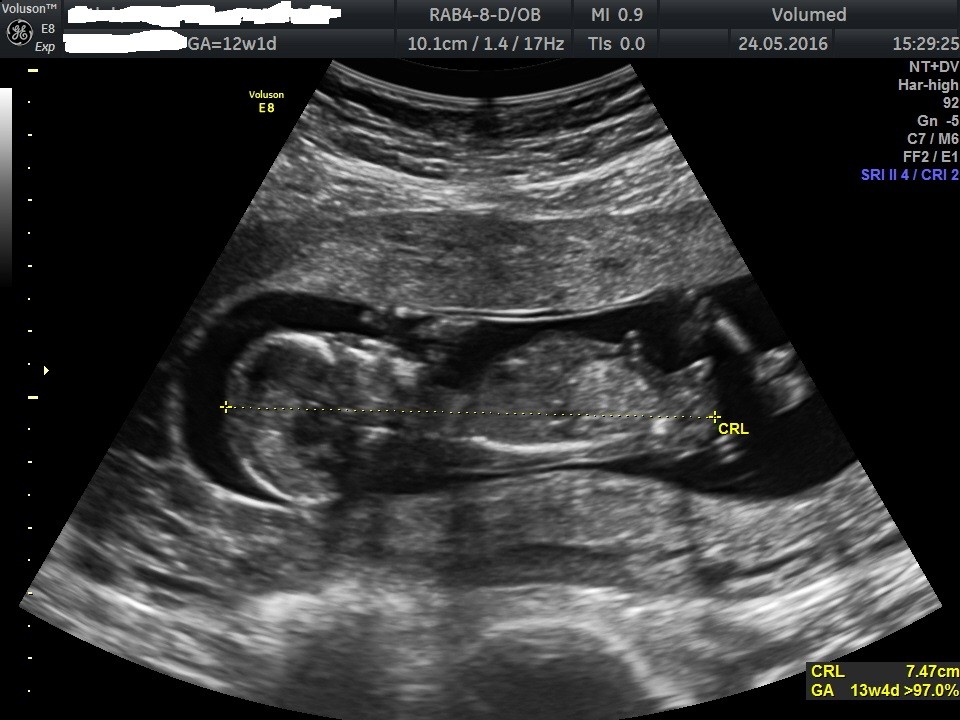

Jak dla mnie dziewczynkaDlaczego ja nie pamiętam tego zdjęcia? Nie no, u twojego nub jest zdecydowanie bardziej chłopcowaty niż u mojej dzidzi.

No Twoj jest zdecydowanie bardziej plaski, ostroznie wrozylabym dziewczynke, ale ja jestem nubowym laik.Dlaczego ja nie pamiętam tego zdjęcia? Nie no, u twojego nub jest zdecydowanie bardziej chłopcowaty niż u mojej dzidzi.